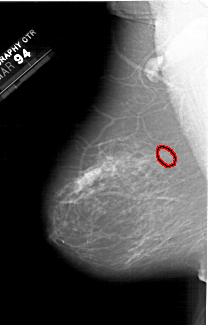

A_1300_1.RIGHT_CC

RIGHT_CC LINES 6346 PIXELS_PER_LINE 3496 BITS_PER_PIXEL 12 RESOLUTION 43.5 NON_OVERLAY

FILE: A_1300_1.LEFT_MLO.OVERLAY

TOTAL_ABNORMALITIES 1

ABNORMALITY 1

LESION_TYPE CALCIFICATION TYPE PUNCTATE-AMORPHOUS DISTRIBUTION CLUSTERED

ASSESSMENT 4

SUBTLETY 4

PATHOLOGY BENIGN

TOTAL_OUTLINES 1